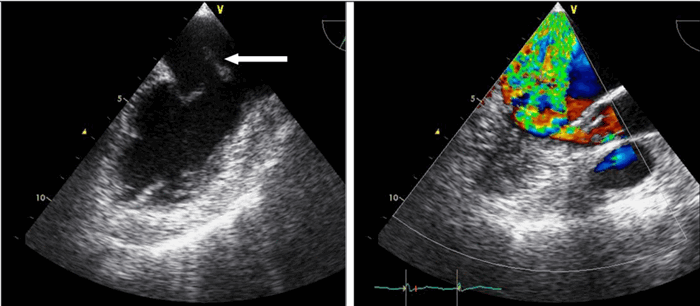

Так, например, эхокардиография с допплерометрией и цветным допплеровским картированием (ЦДК), которая является сочетанием 2D и М-режимов с допплерометрией, очень полезна при оценке митрального стеноза. Первые два способа визуализации позволяют заподозрить кальцификацию клапана (аномальное движение его створок).

Допплерометрия демонстрирует при этой патологии повышенную скорость кровотока (признак сужения) и может быть использована для оценки «эффективной площади отверстия» (степени выраженности стеноза).